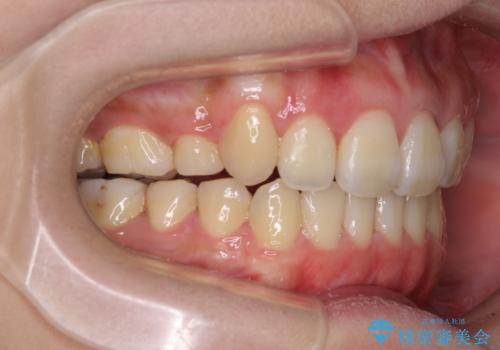

- 八重歯と叢生を気にして来院された患者様です。

上下の前歯が非接触であり、叢生や八重歯が顕著であったため、上顎左右第一小臼歯2本を抜歯して排列することとしました。

抜歯により移動量が多くなるため、ワイヤーや補助装置を活用し、その後インビザラインによる矯正治療を行うこととしました。

元々奥歯に負担のかかる咬み合わせですり減っていたため、仕上がった歯並びでも奥歯が咬んでいないように見えましたが、実際にはしっかりと咬合しており、患者様本人も咬んだ感触に違和感はないとのことでした。